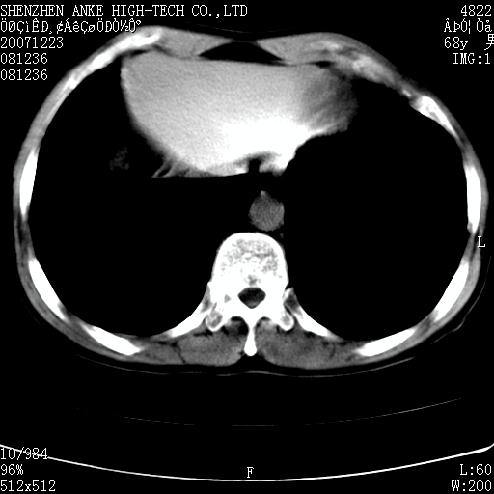

患者:男,63岁,2年前胆囊切除术后,现右上腹部剧烈疼痛近2天.

请看第一张正位片,胸主动脉象有扩张,胸主动脉瘤?